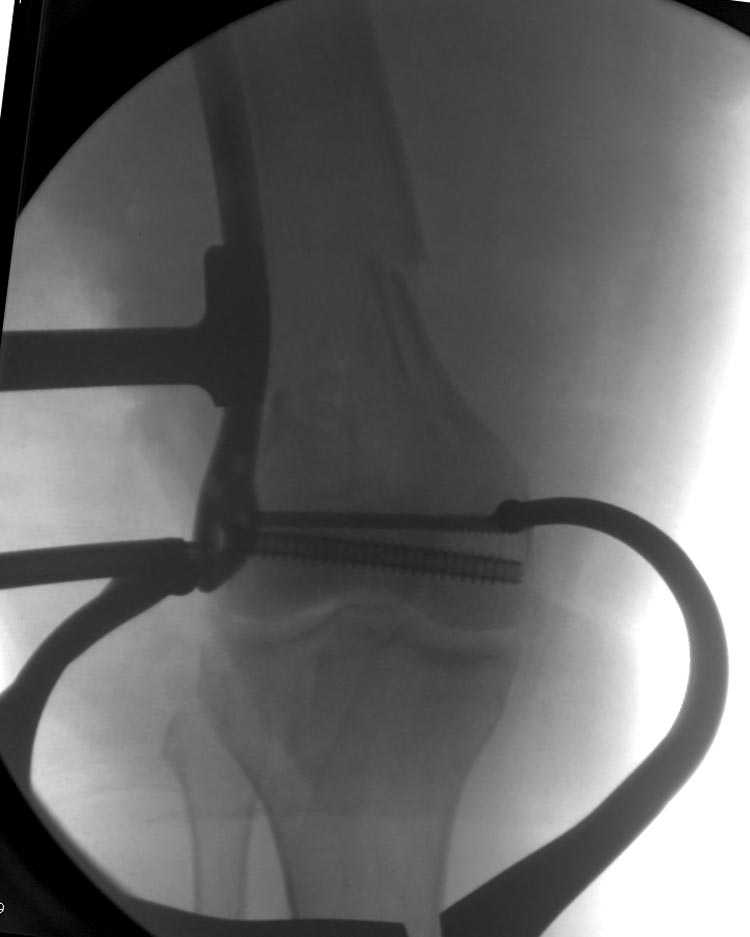

Это перелом не нижней трети, а дистального суставного конца, с распространением на диафиз. Что-то между C2 и C3. Но пока ближе к C2 по увиденному - вторую проекцию еще не показали.

На профиле стало видно, что открываться придется, это перелом C3, хотя можно назвать и C2+, т.е. с еще и фронтальным раскалыванием одного мыщелка. Надо сделать медиальную артротомию, ступеньку на внутреннем мыщелке устранить, ввести либо несколько временных спиц спереди назад, или сразу винт вдоль эллипса мыщелка. А дальше как выше написано - дистрактор, и штифтовать. Учитывая наличие открытого колена - вполне уместно ретроградно.